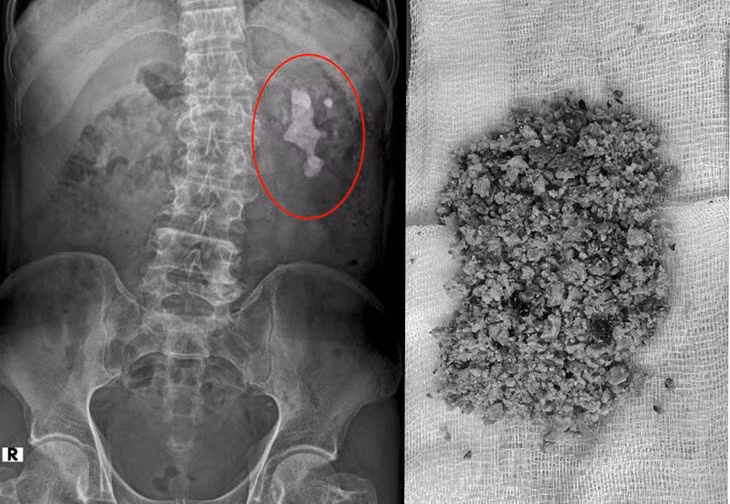

![]() |

| Sỏi thận trên phim chụp và được lấy ra - Ảnh BVCC |